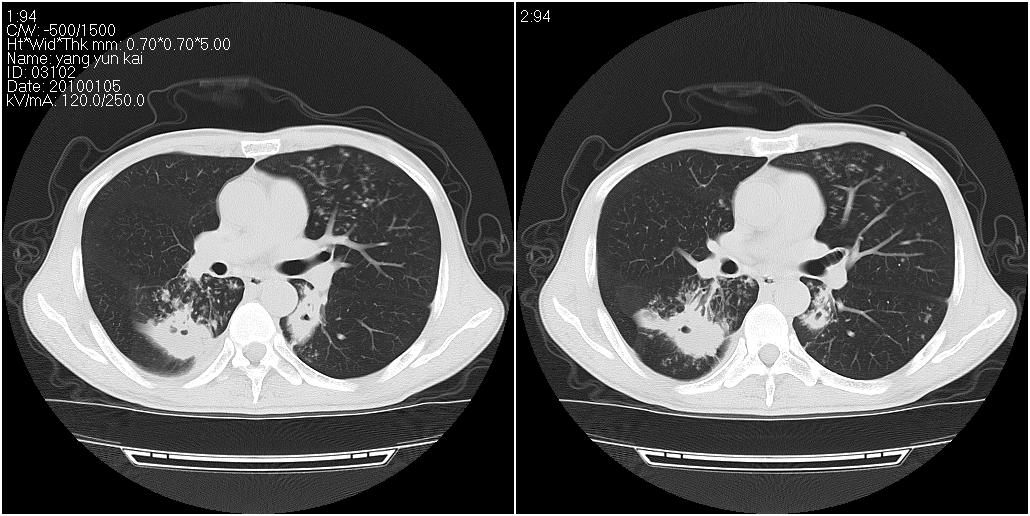

标题: CT23980:男性,47岁。近来咳痰、咳血,血沉增快(40左右),

男性,47岁。近来咳痰、咳血,血沉增快(40左右),痰中未检出结核杆菌。

两肺继发性肺结核并多发性结核球形成,部分病灶内空洞形成。